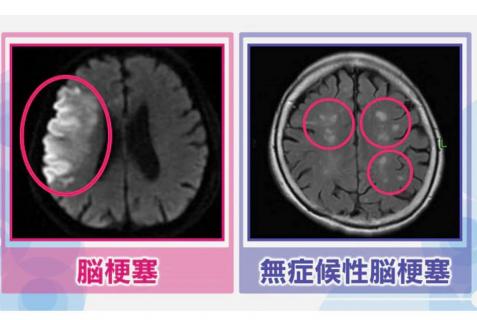

Nhồi máu não là tình trạng các mạch máu trong não bị tắc nghẽn và một phần mô não bị chết. Nhồi máu não thường gây ra các triệu chứng như liệt một bên cơ thể, suy giảm ý thức, rối loạn ngôn ngữ, nhưng nhồi máu não không có triệu chứng thì không gây triệu chứng.

Hình ảnh bên trái được gọi là hình ảnh MRI có trọng số khuếch tán, và nó có đặc điểm là phần thiếu máu do nhồi máu não có màu trắng. Đây là hình ảnh khám của một người đàn ông 70 tuổi bị nhồi máu não phải, ông phải nhập viện vì bị liệt tứ chi bên trái.

Hình ảnh bên phải được gọi là hình ảnh MRI FLAIR. Đây là hình ảnh khám của một phụ nữ 69 tuổi, trên người có nhiều chấm trắng nhỏ, nhưng phần này là nơi xảy ra nhồi máu não không triệu chứng.